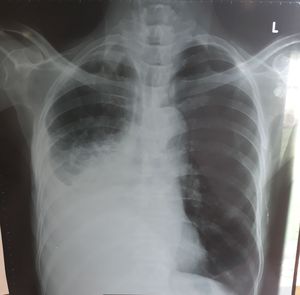

Chest x ray of 71 year old male with history of pulmonary fibrosis